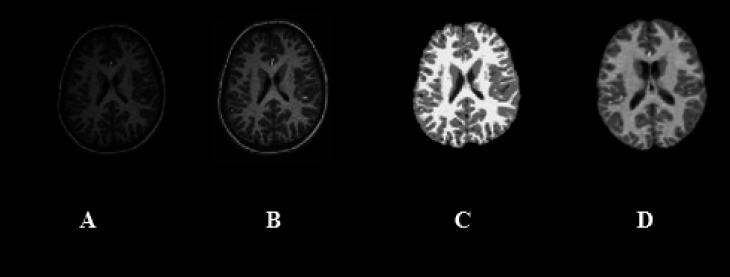

Materials & methods: Surface-based and volume-based features were extracted from FS software and CAT12 toolbox for Statistical Parametric Mapping (SPM) software to estimate ROI-wise biomarkers. These biomarkers were compared between 18 males Typically Developing Controls (TDCs) and 40 male subjects with ASD to assess group differences for each method. Finally, agreement and regression analyses were performed between the two methods for TDCs and ASD groups.

Abstract Image